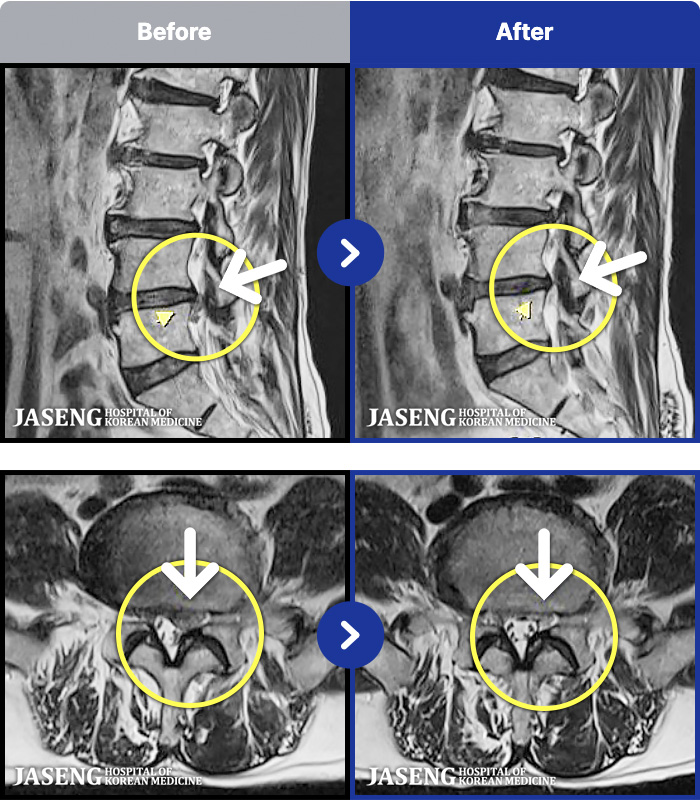

MRI ġ

MRI ũ ʸ Ȯϼ.